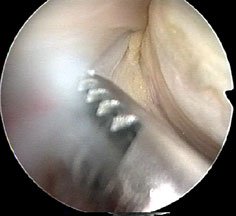

Here are a couple of stills from the video, which just showed a swirling mass of undefinable tissue -